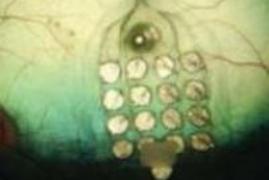

Устройство Argus II было имплантировано 50 пациентов, многие из которых теперь могут видеть цвет, движение объектов. Небольшие камеры, установленные на очках, с помощью портативного процессора переводят сигнал в электрическую стимуляцию на микрочип с электродами, имплантированными непосредственно на сетчатке.

Оказалось, что пациенты сумели считать отдельные буквы менее чем за секунду с 89%-ной точностью. Аналогичные по концепции кохлеарные импланты используются давно. Визуальные имплантаты включают сетку из 60 электродов, подключенных к сетчатке. Ученые из компании-разработчика Second Sight использовали компьютер, чтобы стимулировать шесть точек на сетке и проецировать шрифты Брайля.